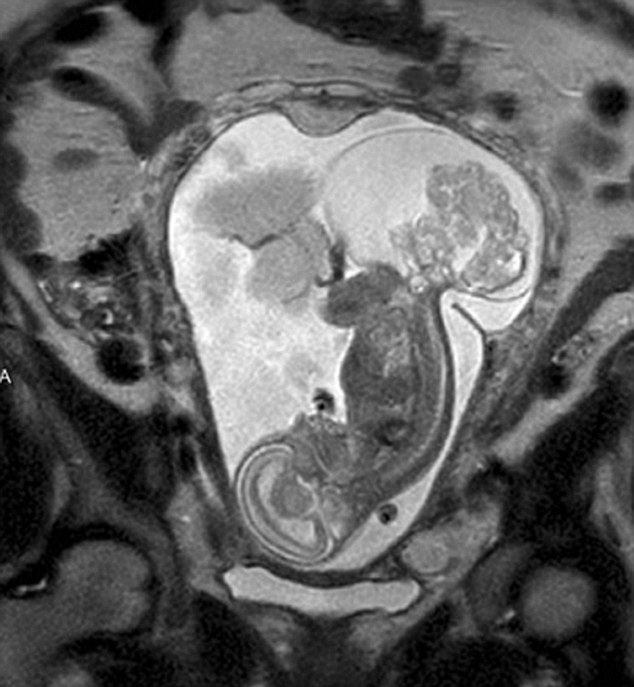

【環球網綜合報道】據英國《每日郵報》10月23日報道,美國得克薩斯州布蘭諾市的女子瑪格麗特·伯默(Margaret Boemer)懷孕16周時去做產檢,不幸被告知胎兒尾骨上長有腫瘤,她與醫生商量后決定先將胎兒取出進行腫瘤切除手術,再將其送回子宮繼續孕育。最終手術圓滿成功,12周后胎兒足月出生。

瑪格麗特稱自己當時聽到產檢結果時十分害怕!搬t生說寶寶長了骶尾部畸胎瘤。我們很震驚,很害怕,因為我們根本不知道這個什么瘤到底意味著什么!彪S著時間流逝,腫瘤越來越大,胎兒滿23周時腫瘤已危及其性命。醫生告訴瑪格麗特,若想胎兒存活,只能將胎兒取出進行手術,然后再放回子宮,否則只能立即終止孕期。“這很容易做決定:讓腫瘤奪去孩子性命,或是給孩子存活的機會。我們當然選擇后者。”瑪格麗特說。

醫生將胎兒取出20分鐘后,便放回母體子宮。12周后,寶寶足月出生,敻覃愄胤Q:“這可以說是她的第二次出生了。只要她有機會活下來,我愿意承受所有風險!(實習編譯:高睿 審稿:朱盈庫)